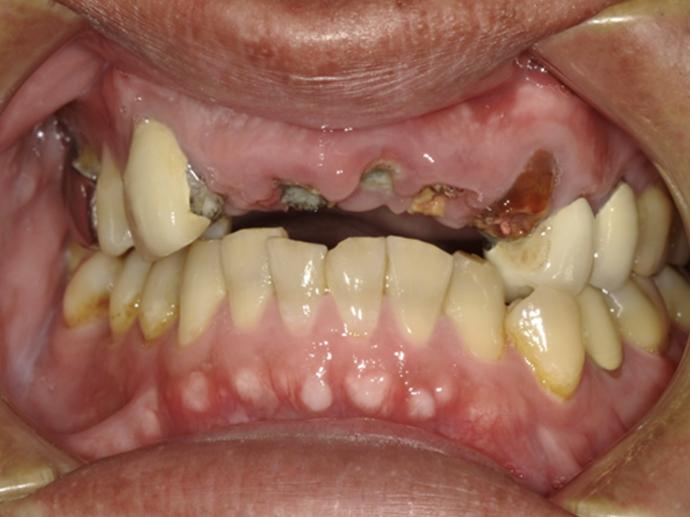

術前  五顆牙齒斷裂    缺牙